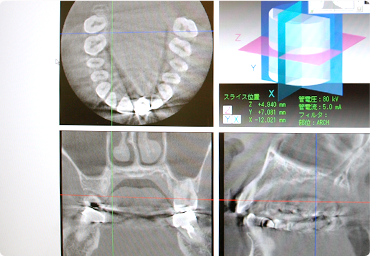

最新のCT機器によって、インプラントを行えるかの状態の確認が、当院で可能です。

インプラントとは?

何らかの理由で失ってしまった歯に、人工の歯根をあごの骨に埋め込み、

その上に人工の歯を入れて回復させる治療です。

インプラント治療には診査が必要です。

口腔内をしっかり診査させていただき、インプラント治療を行っていきます。

まず顎の骨を見るために、レントゲン撮影を行います。

当院は3D CTを完備しているので、他の医療機関でCTを撮影しなくても大丈夫です。

あとは、口腔内の石膏模型・歯周病検査・口腔内写真撮影などです。